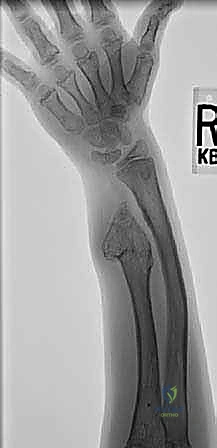

- الأشعة السينية (X-rays): لتقييم حجم الأورام، زاوية انحناء الكعبرة، ومقدار قصر الزند (Ulnar Variance).

- التصوير المقطعي المحوسب (CT Scan): لبناء نموذج ثلاثي الأبعاد للعظام يساعد في التخطيط الجراحي لعمليات القطع العظمي (Osteotomy).